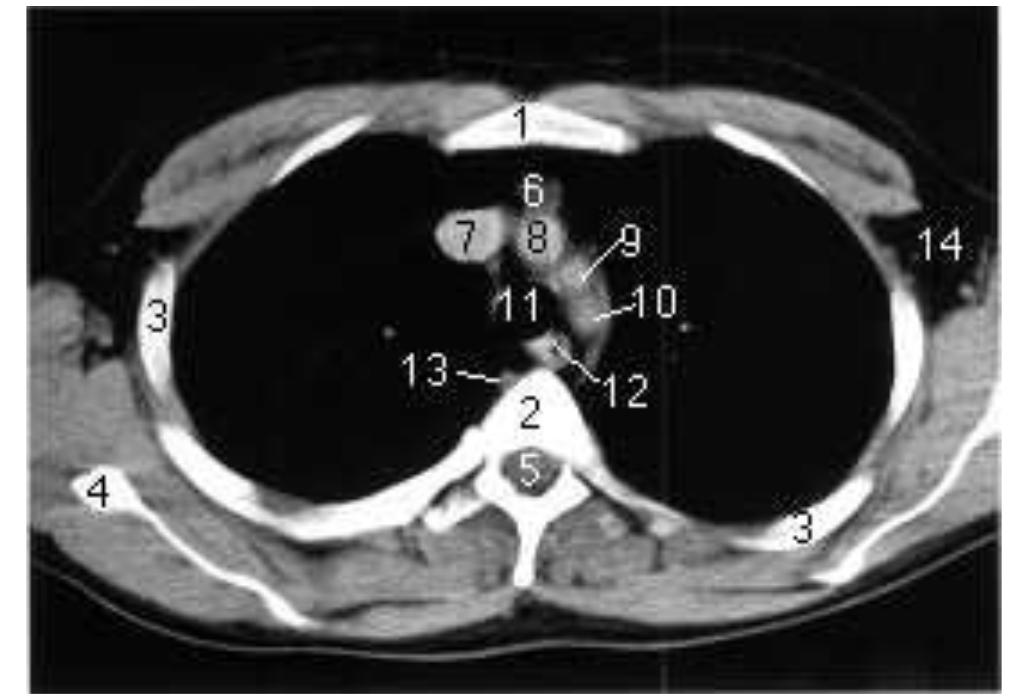

Scanner thoracique, reconstruction axiale

Sternum

corps vertébral

côtes

scapula

canal vertébral

tissu adipeux rétrosternal

veine cave supérieure

tronc brachiocéphalique

artère carotide commune gauche

artère subclavière gauche

trachée

oesophage

veine azygos